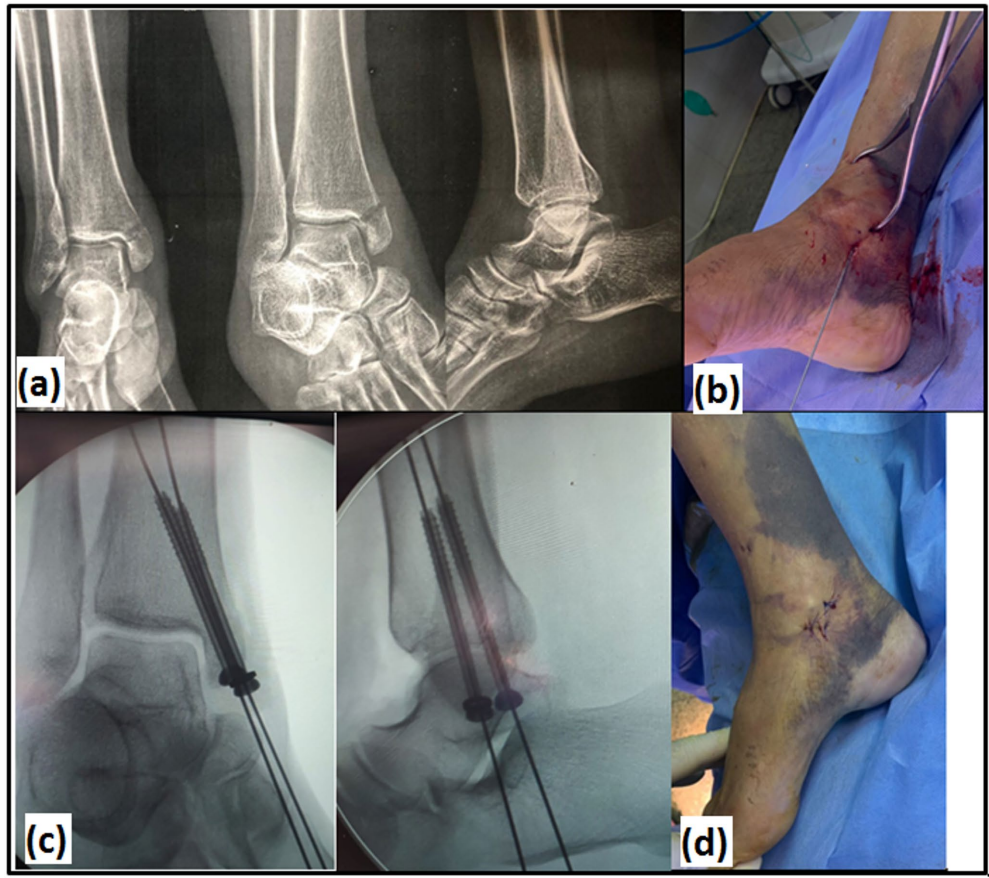

这项发表在《Archives of Orthopaedic and Trauma Surgery》的随机对照试验,首次在严格控制的条件下比较了两种术式——均采用相同的两枚4mm半螺纹空心松质骨螺钉固定。研究纳入50例Herscovici B/C型移位(>2mm)孤立性内踝骨折患者,通过计算机随机分为CRPF组和ORIF组,主要终点为影像学愈合时间和并发症发生率,次要终点包括FAAM(足踝功能量表)、AOFAS(美国足踝外科协会评分)和VAS疼痛评分等功能指标。

关键技术方法包括:1)计算机随机分组和评估者盲法设计;2)标准化手术操作——CRPF组采用尖头复位钳经皮复位,ORIF组采用3-5cm前内侧切口;3)统一使用两枚4mm半螺纹空心螺钉固定;4)通过X线片评估骨折愈合;5)采用FAAM、AOFAS等标准化功能评估工具。所有患者随访12-24个月,确保数据可靠性。